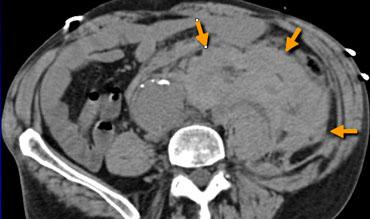

Dấu hiệu động mạch chủ phủ

Bên trái là bệnh nhân nhập viện vì đau lưng.

Hình ảnh ngoài cùng bên trái cho thấy một chỗ phình ra của động mạch chủ.

Đây có thể là biểu hiện của sự yếu khu trú thành động mạch chủ hoặc rò rỉ khu trú.

Thật không may, bệnh nhân này được đọc kết quả là không có rò rỉ và được xuất viện từ khoa cấp cứu.

Hai tuần sau, bệnh nhân bị vỡ phình hoàn toàn.

Dấu hiệu động mạch chủ phủ dương tính được xác định khi có các đặc điểm sau:

- Vùng mà thành sau động mạch chủ không thể xác định được như một đường riêng biệt.

- Phần sau động mạch chủ đi theo đường viền của cột sống ở một hoặc cả hai bên.

Bên trái là một bệnh nhân khác nhập viện vì đau lưng.

Không có bằng chứng rò rỉ túi phình, nhưng chúng ta thấy hình ảnh động mạch chủ phủ.

Đường viền phía sau của động mạch chủ đi theo đường viền của cột sống như thể động mạch chủ đang phủ lên thân đốt sống.

Không có hình ảnh theo dõi ở bệnh nhân này, nhưng ba giờ sau khi chụp hình ảnh này, bệnh nhân đã tử vong do mất máu từ vỡ phình động mạch chủ bụng.

Rò rỉ có thể xảy ra tại vị trí phình ra (mũi tên).